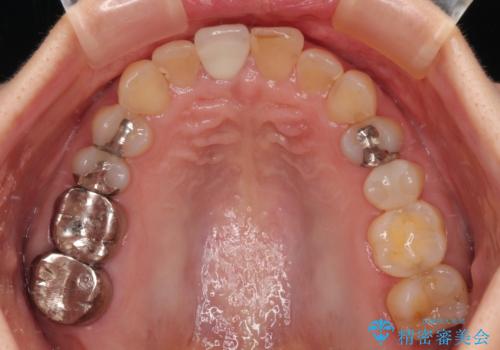

色がやや白いように感じますが、周りの歯をホワイトニングして白くしていくとのことで、明るめの状態での仕上がりとなりました。